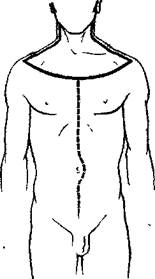

Таким образом, полость живота оказывается широко раскрытой, грудная клетка освобождена от кожи и мышц, шея — от кожи, а отделенные покровы торса в виде огромных лоскутов отвернуты в стороны (рис. 27).

При, сильном развитии мышц живота, при значительном отложении жира или сильном отеке брюшная стенка утолщается и плохо отворачивается в стороны.. Чтобы сделать ее более податливой, над лобком проводят поперечные разрезы брюшины, мышц и жировой клетчатки, не повреждая кожу (рис. 27)..

Рис. 27.

а—разрезы для извлечения языка, глотки, гортани; б—линии рассечения реберных хрящей и грудино-ключичных сочленений.